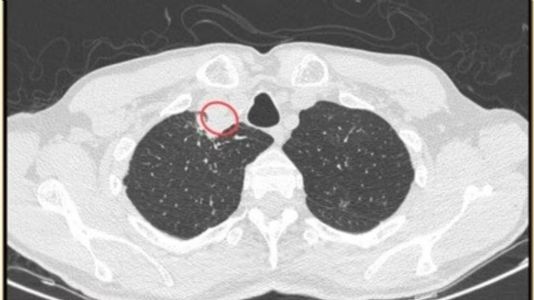

They identified a neck abscess in the man and performed a surgical procedure to drain it and said, "After the surgical procedure, an X-ray examination showed no unusual findings, and the patient was prescribed a round of antifungal medication."